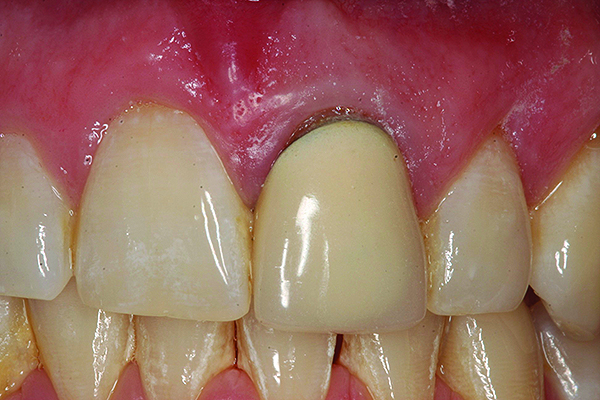

Fig 11. Preoperative photograph.

Figure 11

Fig 12. Postoperative photograph of patient shown in Fig 11 after immediate implant placement with immediate loading, tooth No. 9.

Figure 12

Achieving outstanding esthetics with implant dentistry is a reality (Figure 11 and Figure 12). Restorative efforts require disciplined steps to attain predictable results. To paraphrase my mentor, Cary Shapoff, DDS, renowned for his knowledge of periodontal disease treatment, bone grafting procedures, and dental implant surgery, implant esthetics is a series of well-planned, well-executed small steps that add up to a successfully restored fixture.